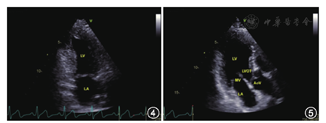

探头置于心尖搏动处,指向右侧胸锁关节,即在心尖四腔心切面基础上将探头逆时针旋转60°左右,直至右侧心腔完全从图像中消失(图4)。

注:LV左心室;LA左心房;LVOT左室流出道;MV二尖瓣;AoV主动脉瓣

图像尖端仍为心尖部,扇面指向心底部,显示左侧心腔和二尖瓣,为从不同角度观察左心腔解剖结构的标准断面之一。

探头位于心尖部,在心尖左心室两腔心切面基础上,探头继续逆时针旋转约60°,直至左心房交界处出现主动脉根部长轴(图5)。

图像显示左心房、左心室、二尖瓣、左心室流出道、主动脉根部以及主动脉瓣。